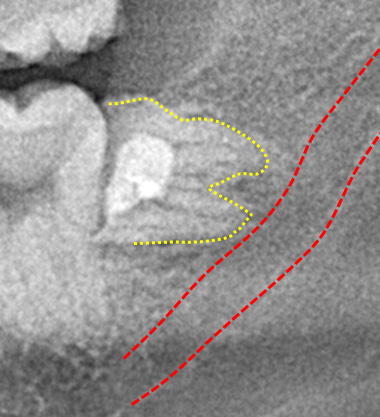

より安全な抜歯のためのCT撮影

パノラマレントゲン撮影で得られる画像は2次元のため、下顎神経の走行や上顎洞と歯の詳細な位置関係を知るのが難しい場合があります。

CT像では歯の生え方や神経の走行、上顎洞との位置関係などを3次元で確認することができるため、より正確な診断が可能です。主治医が総合的に判断しCT撮影を提案された場合はより安全な抜歯のために受けることをお勧めいたします。また患者様のご希望でも撮影は行いますのでお申しつけください。

歯冠切除量と歯根の移動量の結果です。術前の智歯(親知らず)の幅径に対して計測した智歯の長径の割合は1.21ポイント、術後は1.10ポイントで有意に差を認めました。数ヵ月待機することにより歯根は有意に近心側に移動していることを認めました。